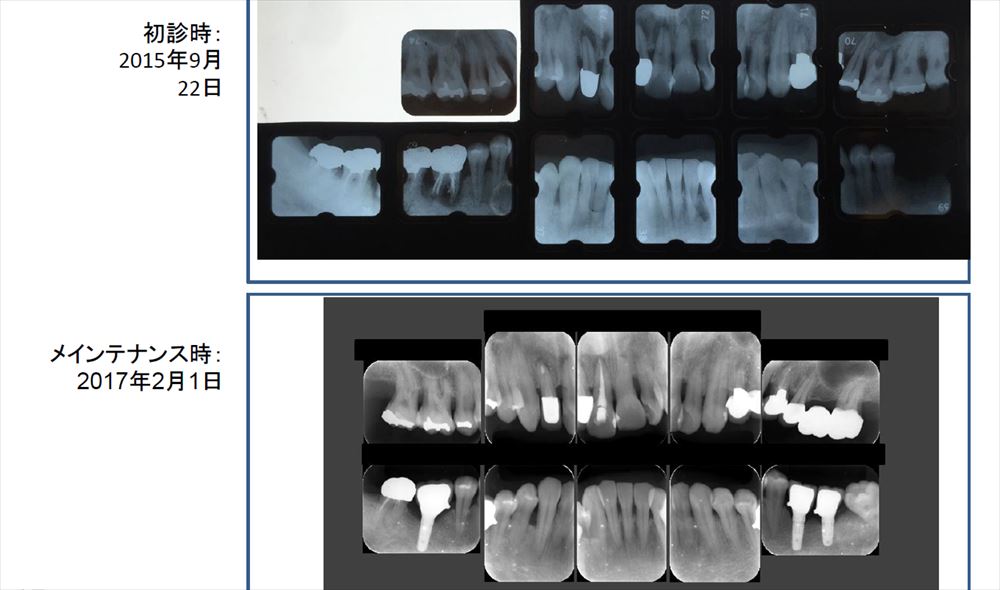

患者さまのブラッシングと私が行ったマイクロスコープを使用した治療で手術もせず無痛で治しています。

こちらはメンテナンス時です。初診と比較し歯茎の色が良くなりました。歯茎も引き締まっていますね。

奥歯にはインプラントも。これで美味しい物が沢山食べれますね!

この様にマイクロスコープを使用する事で重症の歯周病も90%以上手術せず完治させております。